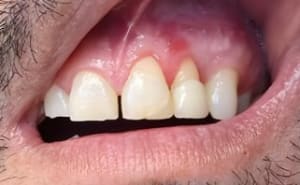

Capture d’écran 2025-10-07 222822.jpg